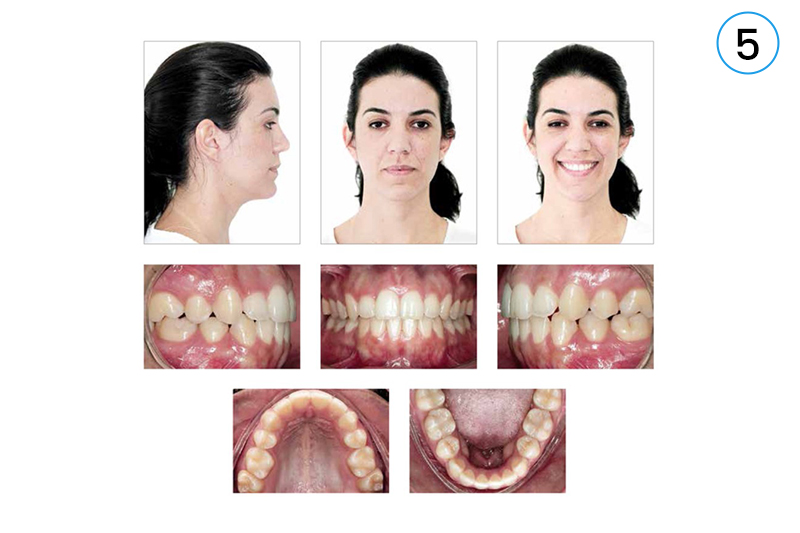

• 5. Intraoral & Extraoral Photographs